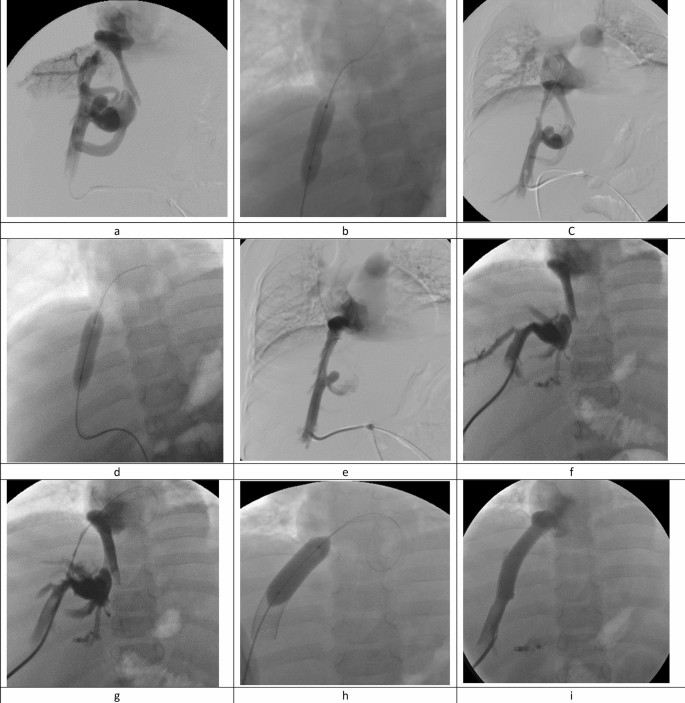

Recanalization of one main HV was sufficient to restore hepatic venous drainage in most of the patients (43/48), while recanalization of 2 HVs was necessary in 5 patients (10.4%). The right HV was most frequently selected as the target vein in 25 patients (52.1%, Fig. 1). Mean free HV pressure (FHVP) significantly decreased from 43.13 ± 6.64 before recanalization to 15.35 ± 2.20 after treatment (P value < 0.001). Descriptive analysis of interventional details is listed in Table 1.

Angiography images of a 15-year-old female patients with FVLM: factor V Leiden mutation (FVLM) with obstruction of the right hepatic vein for 6 months. Transhepatic venography revealed short segment obstruction involving right HV ostium with multiple dilated vascular collaterals (a). Balloon dilatation was performed (b), venography revealed residual stenosis and persistence of collaterals (c). Repeat dilatation was performed (d) and control venography revealed good recanalization of the HV with disappearance of vascular collaterals and without residual stenosis (e). Patient presented with recurrent symptoms 10 months following HV angioplasty, and color Doppler ultrasonography revealed thrombosis of the previously treated right HV. Angiography revealed progressive thrombosis of the treated HV compared to the primary intervention with vascular collaterals (f). The obstruction was bypassed using a transhepatic approach (g) followed by stent insertion (h). Final venography following stent dilatation revealed free flow of contrast agent across the stent with disappearance of intrahepatic collaterals (j).